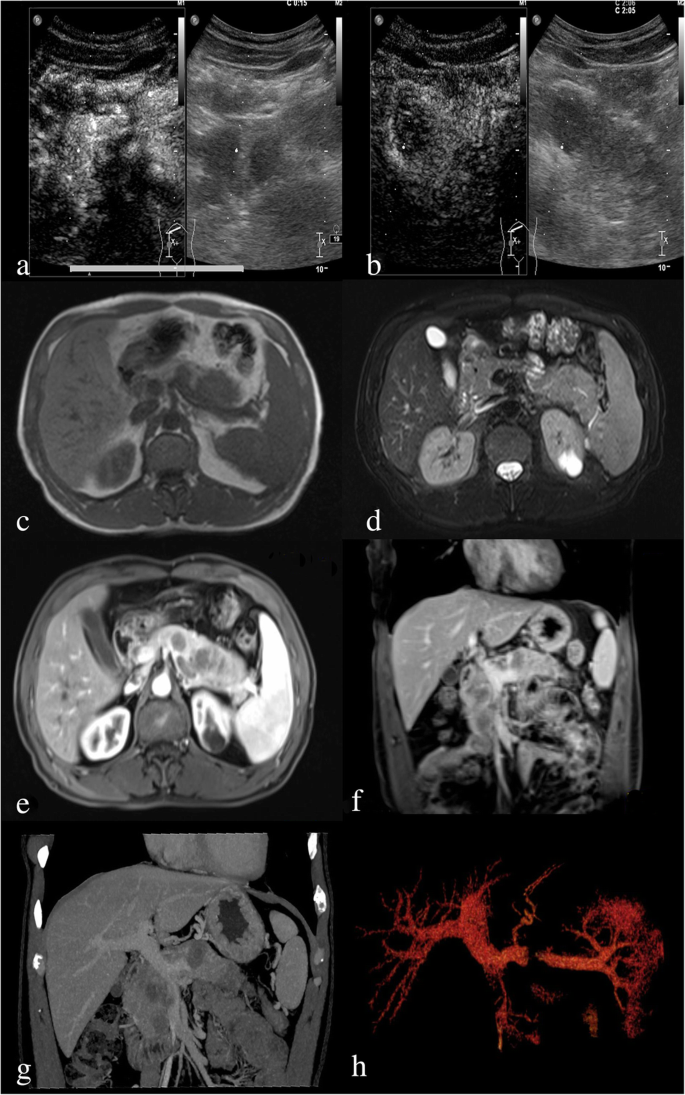

A 43-year-old man presented to our hospital with a 10-day history of mild epigastric pain, without weight loss or jaundice. This patient had a medical history of acute pancreatitis about 6 months before the current admission. He had a cystic neoplasm in the pancreatic tail 4 months later and was diagnosed with pancreatic pseudocysts at a local hospital. He was a non-smoker and denied any history of prior surgery. After admission, a mass was palpated on the left upper abdomen during physical examination. Routine laboratory tests results for liver function and pancreatic amylase were normal. The tumor markers of carcinoembryonic antigen, carbohydrate antigen 19–9, and carbohydrate antigen 125 were also within normal limits. Abdominal contrast-enhanced ultrasonography revealed multifocal hypoechoic mass in the pancreas (Fig. 1a and b). Magnetic resonance imaging (MRI) of the upper abdomen revealed multifocal masses occupying the entire enlarged pancreas. The lesions were hypointense on T1-weighted image (Fig. 1c) and isointense on T2-weighted image (Fig. 1d). The lesions were heterogeneously enhanced during the arterial phase and portal venous phase (Fig. 1e, f). Contrast-enhanced computed tomography (CT) also showed that these lesions were multifocal with low density and the largest one had a diameter of 2.6 cm (Fig. 1g). Three-dimensional vascular reconstruction of CT showed that a tumor thrombus formed in the superior mesenteric vein and central segment of the splenic vein (Fig. 1h).